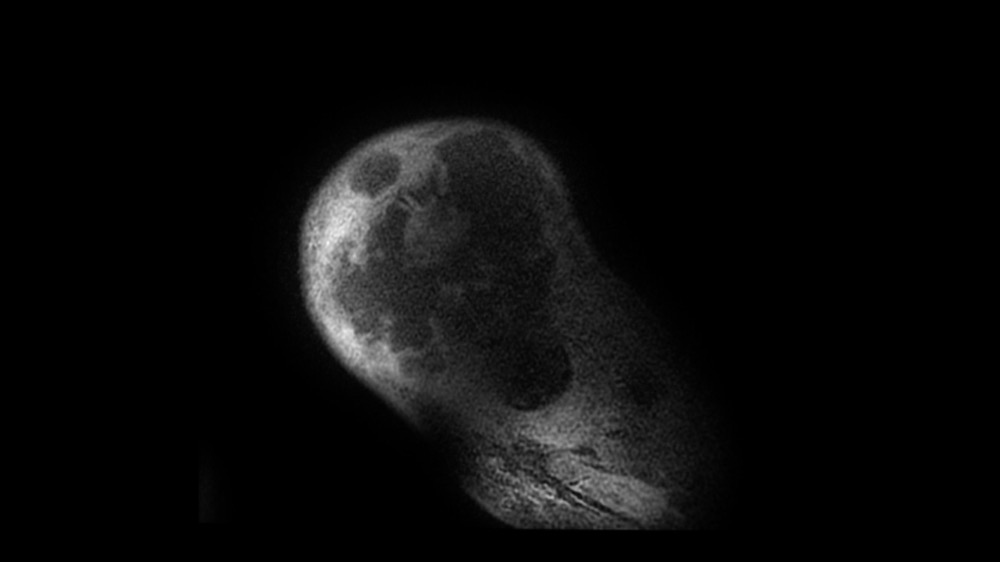

Bone Club

Bernard Hollier 18/05/2022